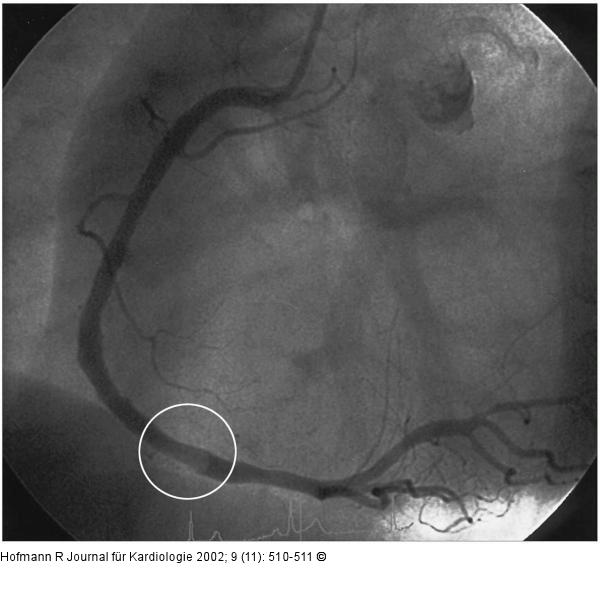

Abbildung 3: Mobiler Thrombus in der RCA bei NSTEMI Angiogramm der rechten Koronararterie: diffuse nichtstenosierende sklerotische Veränderungen; Kontrastmittelübertragungsdefekt im mittleren Drittel (Kreis). |

Angiogramm der rechten Koronararterie: diffuse nichtstenosierende sklerotische Veränderungen; Kontrastmittelübertragungsdefekt im mittleren Drittel (Kreis). |